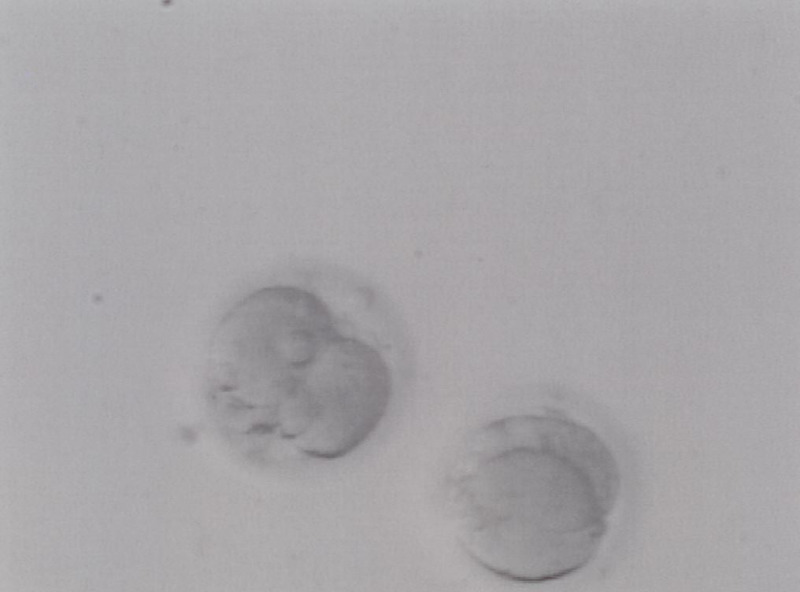

Unsere Tochter ist übrigens "bumperl gesund" und ein prächtig entwickeltes Mädchen. Es ist faszinierend, das die befruchtete Eizelle bei ca. -200°C eingefroren wurde und nun ein kleines Menschlein daraus geworden ist :)

Eine von den beiden Eizellen ist übrigens unsere Tochter, toll das wir bereits in dem Stadium ein "Foto" von ihr haben :P